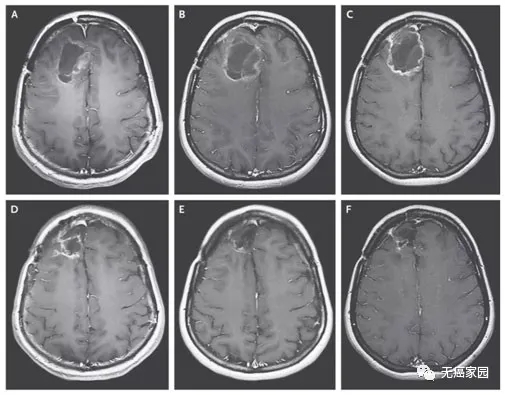

2018年6月26日,一篇发表在顶尖医学杂志上的《NEJM》上的研究引起广泛关注,美国杜克大学癌症研究所的科学家们,采用一种经过改造的脊髓灰质炎病毒(PVSRIPO),显著延长了脑胶质母细胞瘤患者的生命。

截止2018年3月20日,8名患者对治疗产生治疗应答,2名患者的脑胶质瘤病灶完全消失,达到了完全缓解!目前,PVSRIPO正在美国几所知名的癌症中心,包括麻省总医院,丹娜法伯癌症研究所等进行二期临床试验,仍在招募中。要想了解更多关于溶瘤病毒的国内外临床研究请咨询无癌家园医学部400-626-9916。